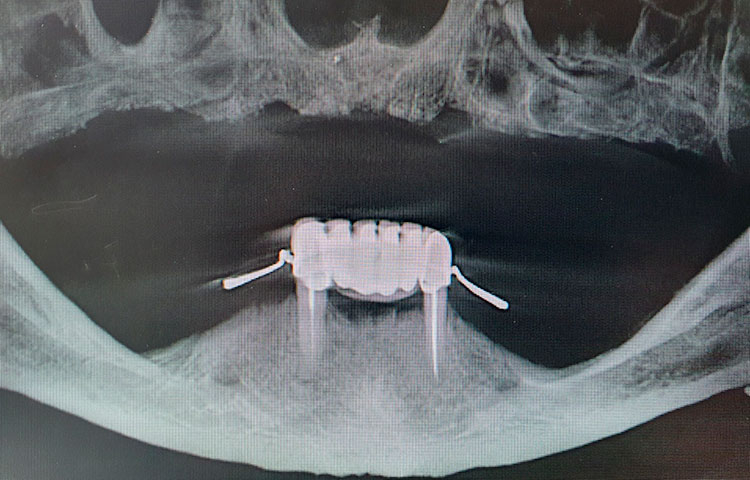

Данные КТ–диагностики: наблюдается сильная атрофия кости в боковых отделах верхней челюсти, остаточная кость в проекциях 14-17 и 24-27 около 2 мм. В переднем отделе костная ткань около 10 мм по высоте, по ширине определяется сильная атрофия.

Под местной анестезией по ранее изготовленному хирургическому шаблону установлены 4 импланта Medentika Quadroconne (3.8х09 в область 1.1, 2.1, 4.3х11 в область 1.3, 2.3 под углом 30 гр.), получен необходимый торк, установлены мультиюниты, получен оттиск для изготовления временного пластмассового протеза. Установлены защитные колпачки, рана ушита. Даны назначения (Антибиотики, НПВС).

КТ после фиксации